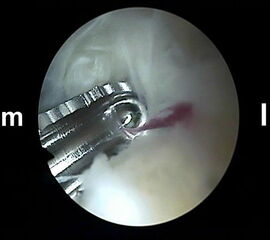

Abbildung Nr. 5-7

Über das laterale Portal wird ein 4,0 mm Arthroskop senkrecht nach ventral eingebracht mit der Zielrichtung auf den 1. Interdigitalraum. Zur Orientierung kann mit dem stumpfen Wechselstab zunächst der Kontakt zum Knochen getastet werden. Es lassen sich so auch die dorsale Tibiakante, der Proc. posterior des Talus und die craniale Begrenzung des Kalkaneus identifizieren. Ist das Arthroskop über das laterale Portal eingeführt, wird die Blickrichtung nach lateral ausgerichtet. Von medial wird ein Weichteilshaver eingeführt, dessen Arbeitsöffnung nach ebenfalls lateral weist. Die Instrumente werden in der Weise trianguliert, dass die Shaverspitze unmittelbar vor dem Arthroskop identifiziert werden kann (rechte Seite, m=medial, l=lateral).